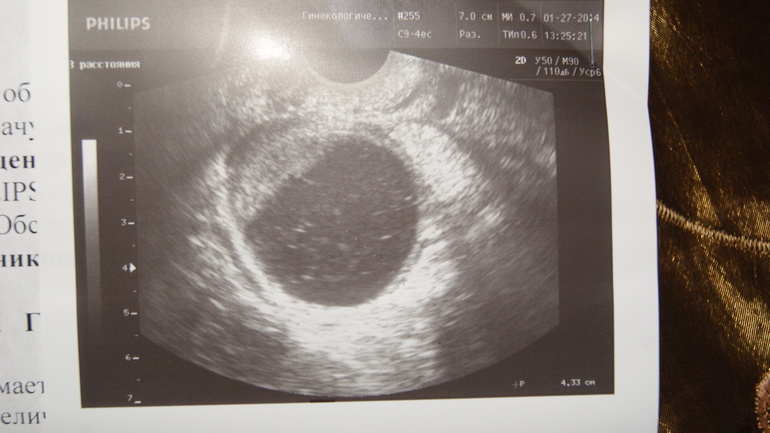

нет,что случилось с правым Я его нет,она его не нашла,размеры меня не пугают бывало и больше...

мне только в сентябре удалили кисту с этого Я, они просто даже не на своих местах,тут сказано что левый за шейкой а правого нет вообще...

так там размеры Я такие что правого вообще не видно,меня не киста а Я беспокоит,яичник упал к шейке матки, закрыл собой даже матку....Г разводит руками....

загнут может быть из за спаек,а тут левый упал за ШМ,а правого вообще нет!!!!